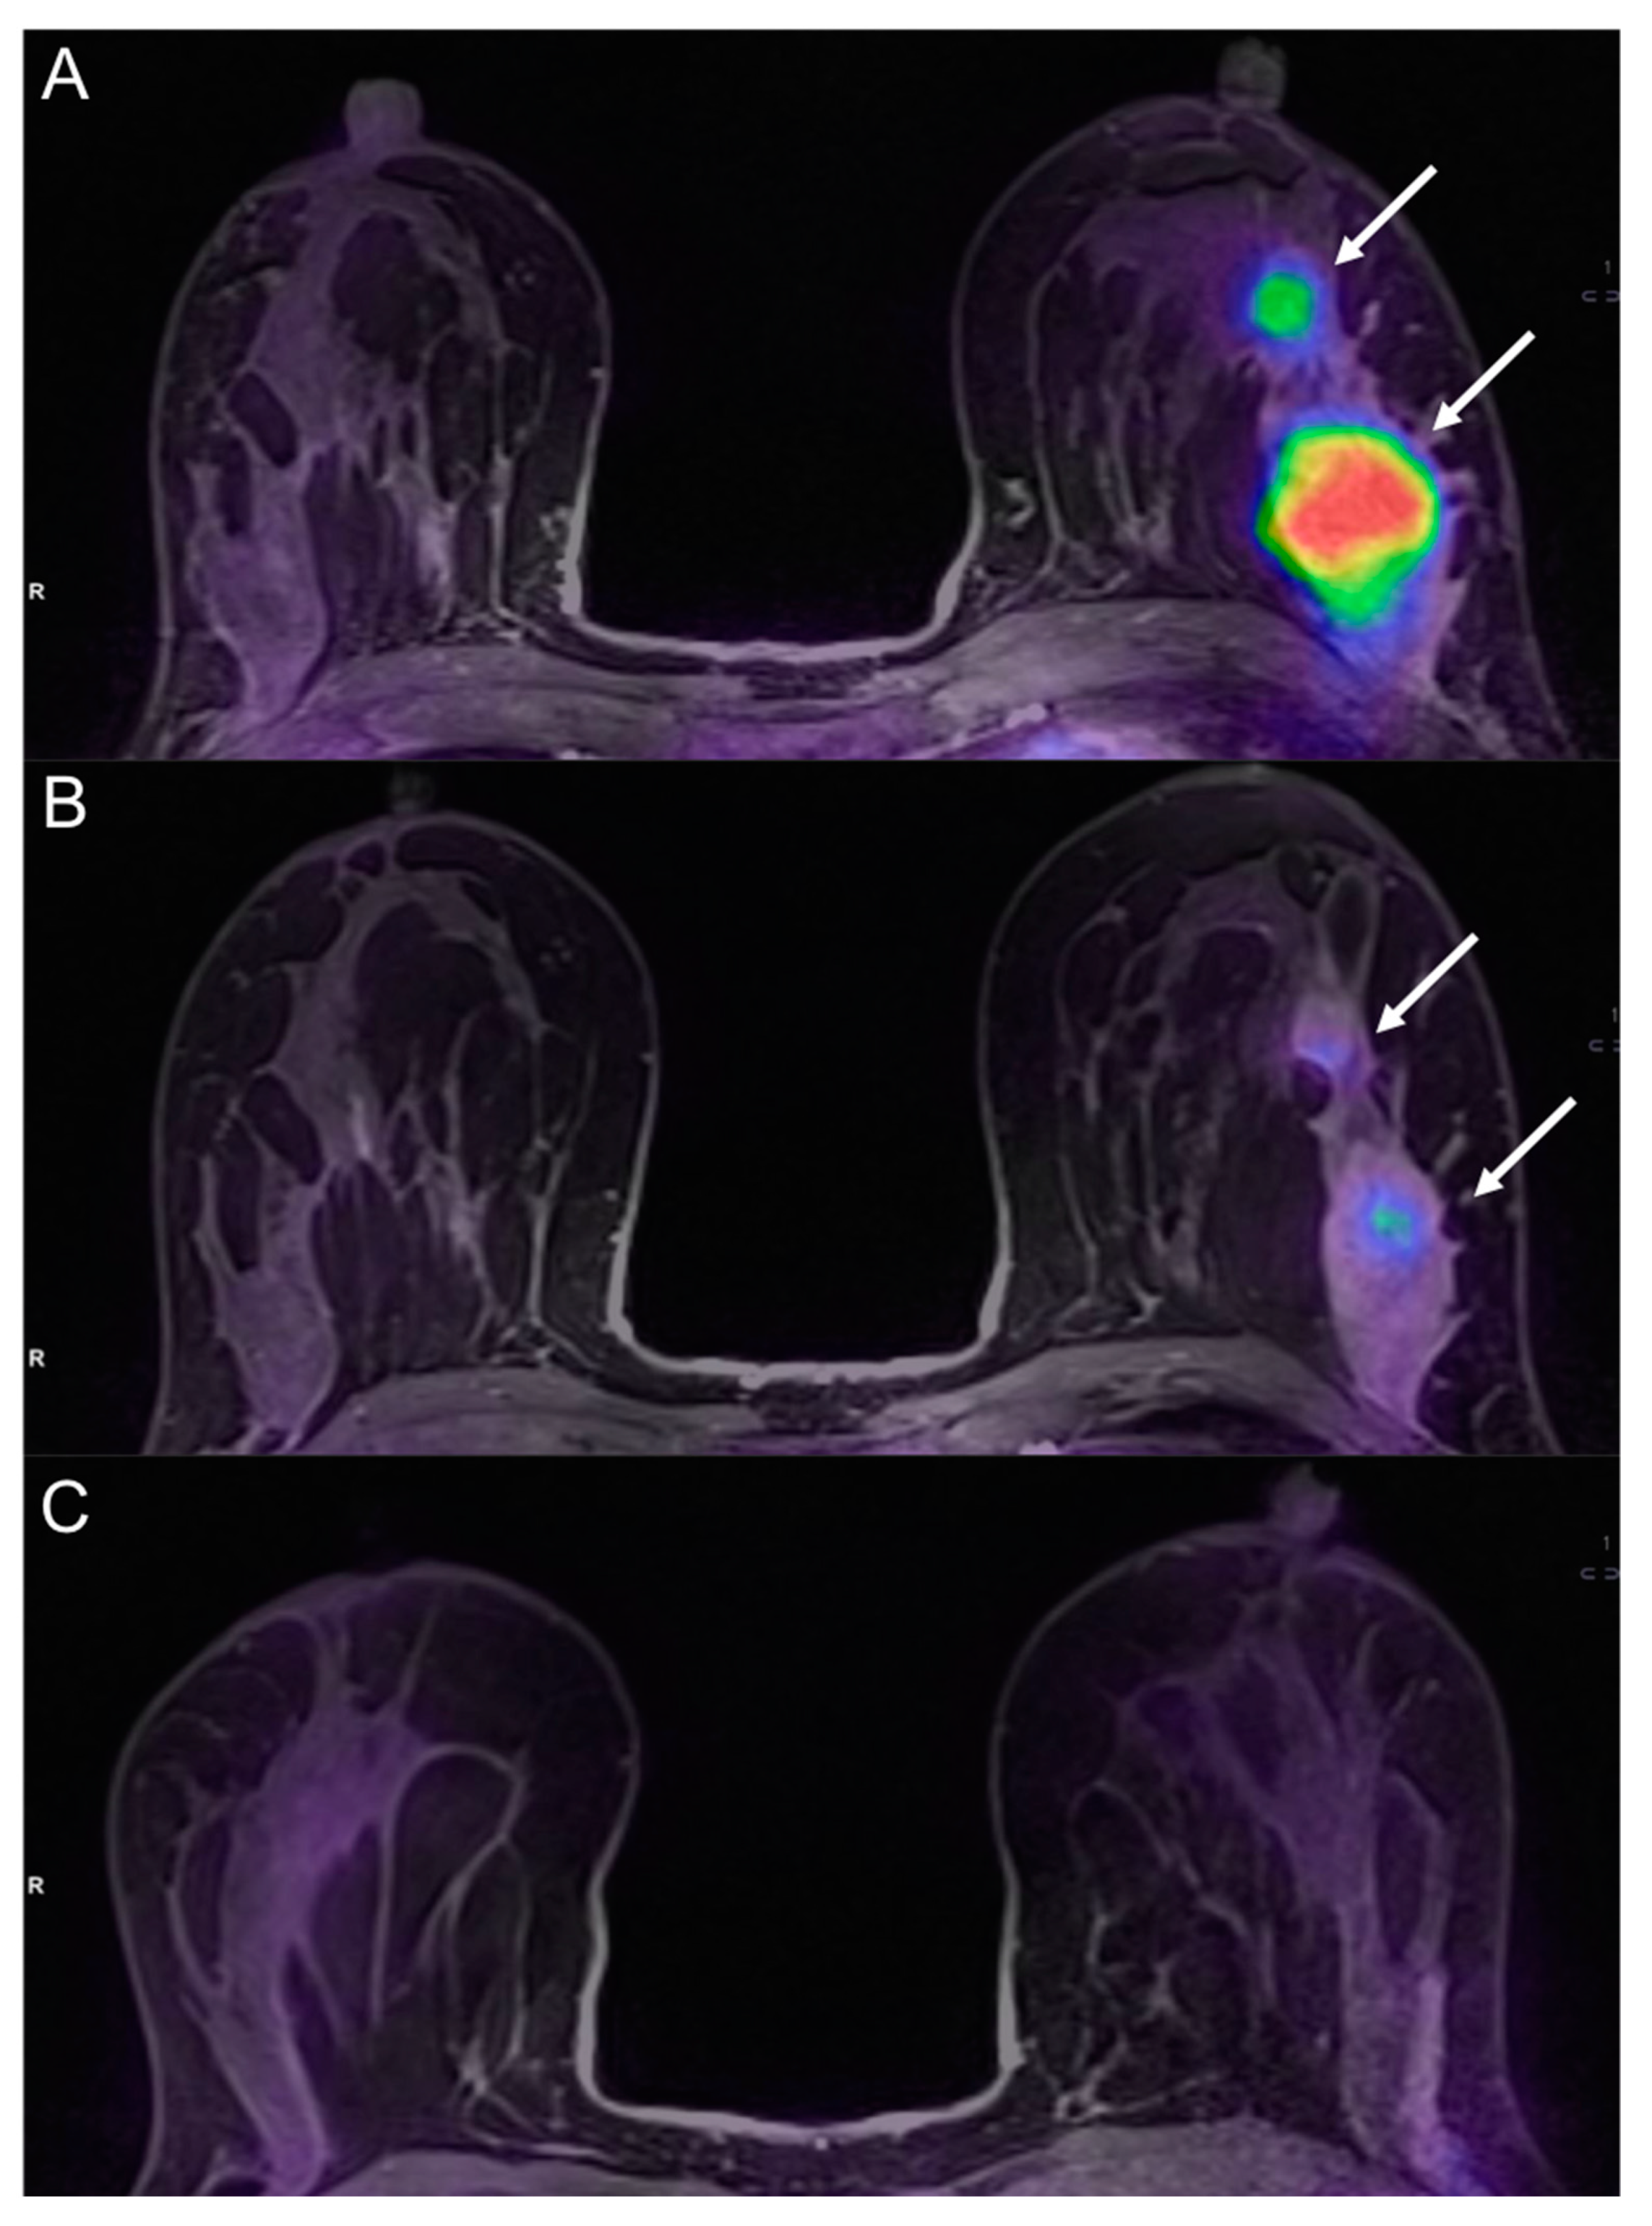

- Romeo, V.; D’Aiuto, M.; Frasci, G.; Imbriaco, M.; Nicolai, E. Simultaneous PET/MRI assessment of response to cytotoxic and hormone neo-adjuvant chemotherapy in breast cancer: A preliminary report. Med Oncol. 2016, 34, 18. [Google Scholar] [CrossRef]

- Cho, N.; Im, S.-A.; Cheon, G.J.; Park, I.-A.; Lee, K.-H.; Kim, T.-Y.; Kim, Y.S.; Kwon, B.R.; Lee, J.M.; Suh, H.Y.; et al. Integrated 18F-FDG PET/MRI in breast cancer: Early prediction of response to neoadjuvant chemotherapy. Eur. J. Nucl. Med. Mol. Imaging 2017, 45, 328–339. [Google Scholar] [CrossRef] [PubMed]

- Wang, J.; Shih, T.T.-F.; Yen, R.-F. Multiparametric Evaluation of Treatment Response to Neoadjuvant Chemotherapy in Breast Cancer Using Integrated PET/MR. Clin. Nucl. Med. 2017, 42, 506–513. [Google Scholar] [CrossRef] [PubMed]

- Pengel, K.E.; Koolen, B.B.; Loo, C.E.; Vogel, W.V.; Wesseling, J.; Lips, E.H.; Rutgers, E.J.T.; Olmos, R.A.V.; Peeters, M.J.T.F.D.V.; Rodenhuis, S.; et al. Combined use of 18F-FDG PET/CT and MRI for response monitoring of breast cancer during neoadjuvant chemotherapy. Eur. J. Nucl. Med. Mol. Imaging 2014, 41, 1515–1524. [Google Scholar] [CrossRef] [PubMed]

- An, Y.Y.; Kim, S.H.; Kang, B.J.; Lee, A.W. Treatment Response Evaluation of Breast Cancer after Neoadjuvant Chemotherapy and Usefulness of the Imaging Parameters of MRI and PET/CT. J. Korean Med. Sci. 2015, 30, 808–815. [Google Scholar] [CrossRef] [PubMed]